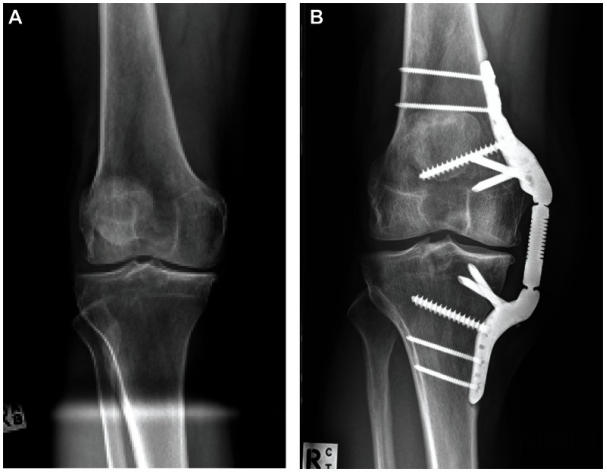

(A) 术前前后位 X 光片显示内侧隔室明显的骨关节炎;(B) 植入后 2 年的 KineSpring 膝关节植入系统

随着技术发展,KineSpring进化为Atlas Knee System,并于2015年11月获得CE认证和商业化运用。一年后,第一批美国膝关节OA患者接受了Atlas治疗。